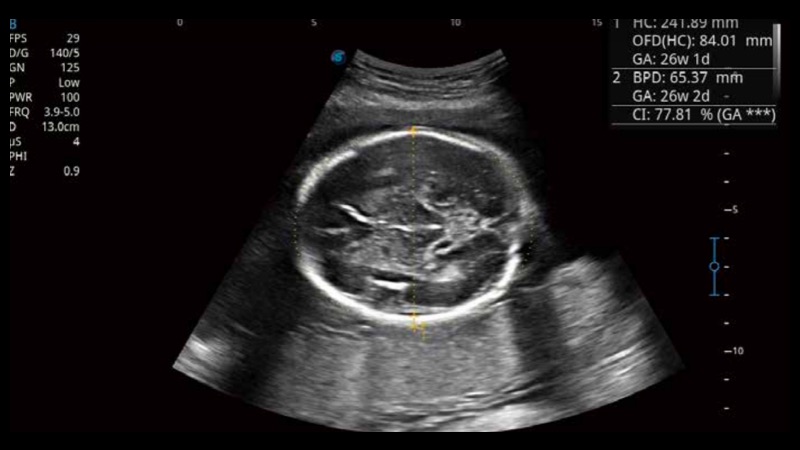

Based on a big data dependable deep learning algorithm, S-Fetus is a brilliant one-step solution for automatic standard plane acquisition and measurement. With just one click, common fetal biometry results are obtained with high intelligence, accuracy and efficiency, aiming for an unprecedented ease during operation.

Less keystroke required while achieving more sensitive and advanced automated common fetal biometry.